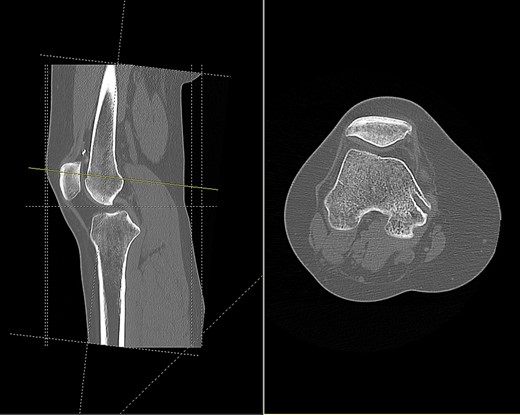

Imaging enabled assessment of the graft tunnels (Figs 2 and 3). It appeared that an oblique tunnel had been drilled from the medial epicondyle to the anterior cortex of the femur at the level of the suprapatellar fat pad.

CT scan of the right knee showing entry point and oblique path of femoral tunnel at medial epicondyle (sagittal and axial view).